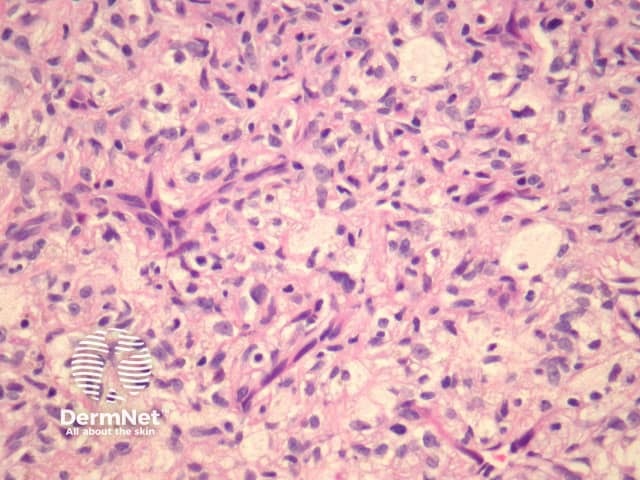

Atypical dermatofibroma is also known as dermatofibroma with monster cells or pseudosarcomatous dermatofibroma. There are focal areas within a common dermatofibroma consisting of large polymorphous cells with large nucleoli (‘monster cells’) (figures 9, 10).

Atypical dermatofibroma can be aggressive with rare reports of metastasis and death. However, many of these cases were described before modern immunohistochemical studies were available and may now be reclassified as sarcomas.

Figure 9

Figure 10